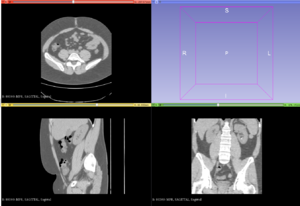

- 1.39 Advances in Stereotactic Navigation for Pelvic Surgery